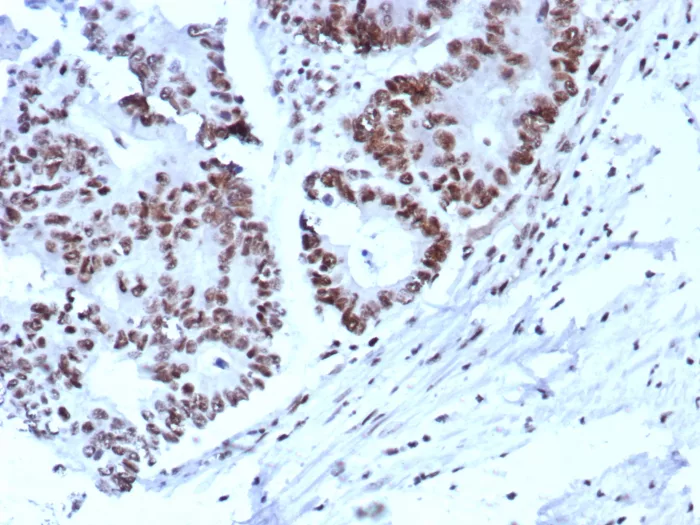

IHC analysis of formalin-fixed, paraffin-embedded human colon. Strong nuclear staining using KIP2/8572 at 2ug/ml in PBS for 30min RT.